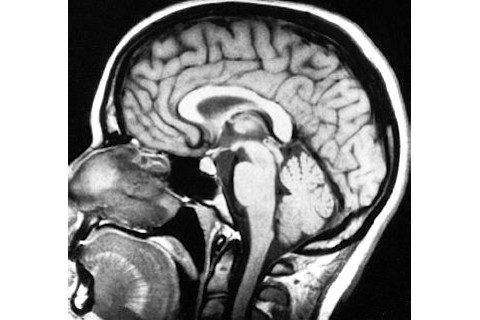

Now that I'm finally back in Durham, I must express tremendous gratitude to the incredible group of researchers working at New York University's Poeppel lab for all of their assistance, encouragement, humor, and fine hospitality during my stay as we spent all week scanning subjects brains for The Kissing Experiment. I'd like to individually thank Katherine Yoshida who set up the trials for her many tireless hours working with photos. I'm appreciative to Tobias Overath for his patience in the MRI and Christine Boylan for her head curviture assessments. Also, I'm grateful to Jeff Walker for running each trial and Discover's own Amos Zeeberg and Eliza Strickland for willing to be my guinea pigs and braving the MEG machine. Most importantly, very special thanks to Gregory Cogan for being a terrific host and David Poeppel (

) for allowing me to take over his lab for such a stimulating cognitive neuroscience experiment. We're already seeing some very interesting results which I'll have plenty to say about here and in the book. For more on David's research, you can check out his terrific blog called Talking Brains. The Poeppel lab is an incredible group and I already miss them and NYC! XX